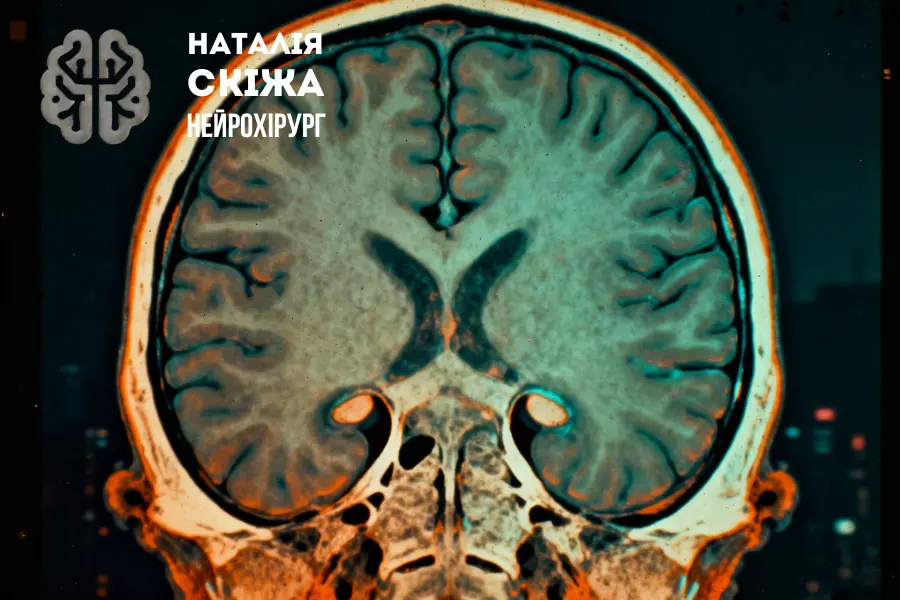

Комп’ютерна томографія головного мозку — це сучасний метод візуалізації, який використовує рентгенівські промені та комп’ютерну обробку для отримання пошарових знімків мозкових структур. На відміну від традиційної рентгенографії, КТ дозволяє детально вивчити внутрішню анатомію, оцінити тканини, шлуночкову систему мозку, кістки черепа і судинні структури.

При скануванні рентгенівська трубка обертається навколо голови пацієнта, а надчутливі сенсори фіксують проходження променів через тканини. Дані перетворюються у високоточні 2D та 3D-зображення. Це дає можливість побачити навіть невеликі патологічні зміни — від крововиливу до новоутворень.